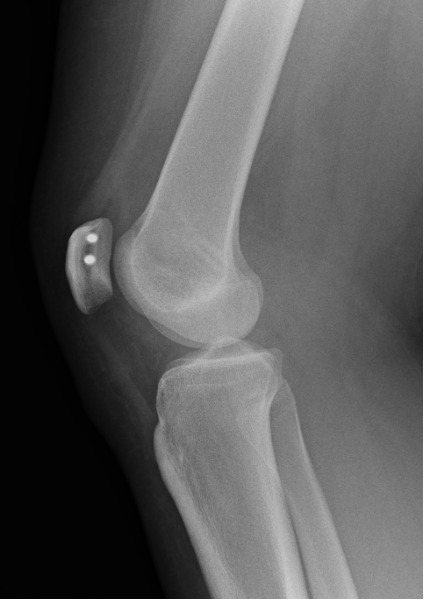

This is the work horse surgery of any kneecap dislocation. MPFL is a ligament that attaches the kneecap to the femoral condyle on the inner side of thigh and is responsible for stabilising the patella to glide on the trochlea especially in the initial stages of knee bending. The function of this ligament can be compared to the reins of a horse – Just like the reins of a horse control the movement of the horse, the MPFL controls the movement of the patella in the trochlea. MPFL reconstruction surgery replaces the native MPFL ligament by a stronger ligament (hamstring tendon) that keeps the patella (kneecap) in place (see image below). The ligament is typically harvested from the hamstrings tendons running on the back of the thigh, by an incision over the inner site of the shin bone (tibia).